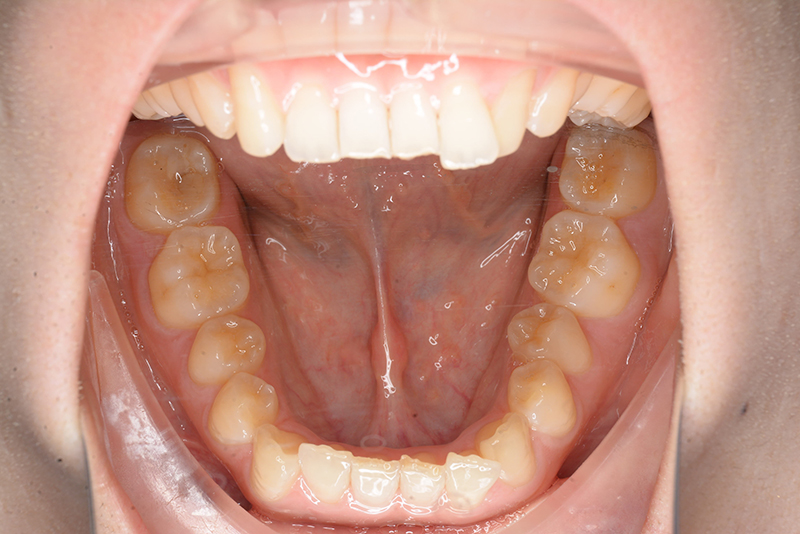

動的治療時(PLASによる上顎歯列遠心移動)

動的治療時

(PLASによる上顎歯列遠心移動)

IOP